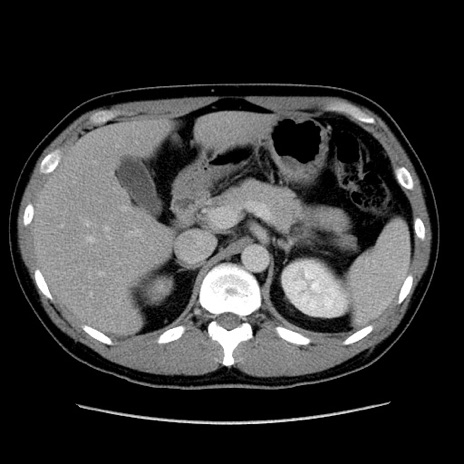

冠状断像

【症例】30歳代男性

【主訴】腹痛、嘔吐

【現病歴】昨晩から突然の腹痛あり、その後嘔吐、軟便も出現。腹痛が改善しないため救急搬送となる。2日前にしめ鯖の食事歴あり。

【身体所見】意識清明、苦悶様、BP 135/90mmHg、BT 35.7℃、腹部:平坦、やや硬、心窩部〜臍部に自発痛、圧痛あり、筋性防御+、反跳痛-

【データ】WBC 8100、CRP 0.57